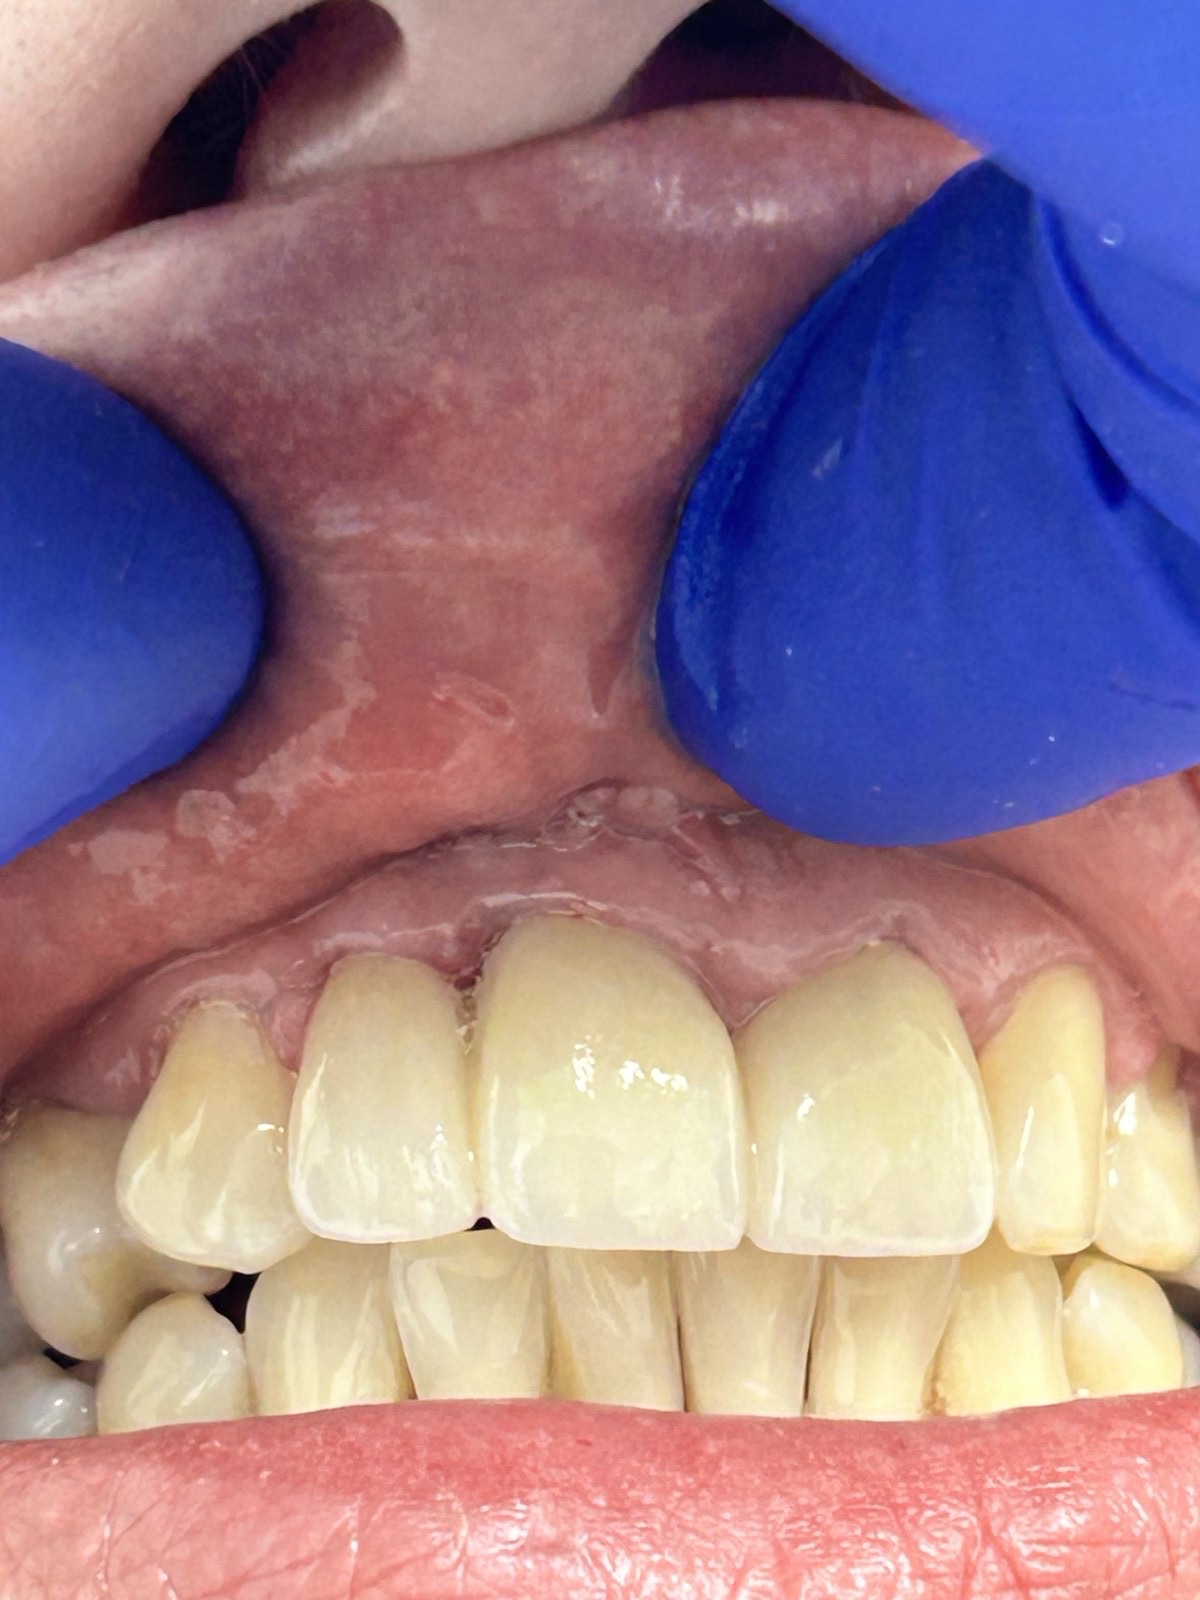

Пациентке предложено протезирование зубов коронками из диоксида циркония.

Работу выполнил стоматолог-ортопед Бернович Дмитрий Иосифович